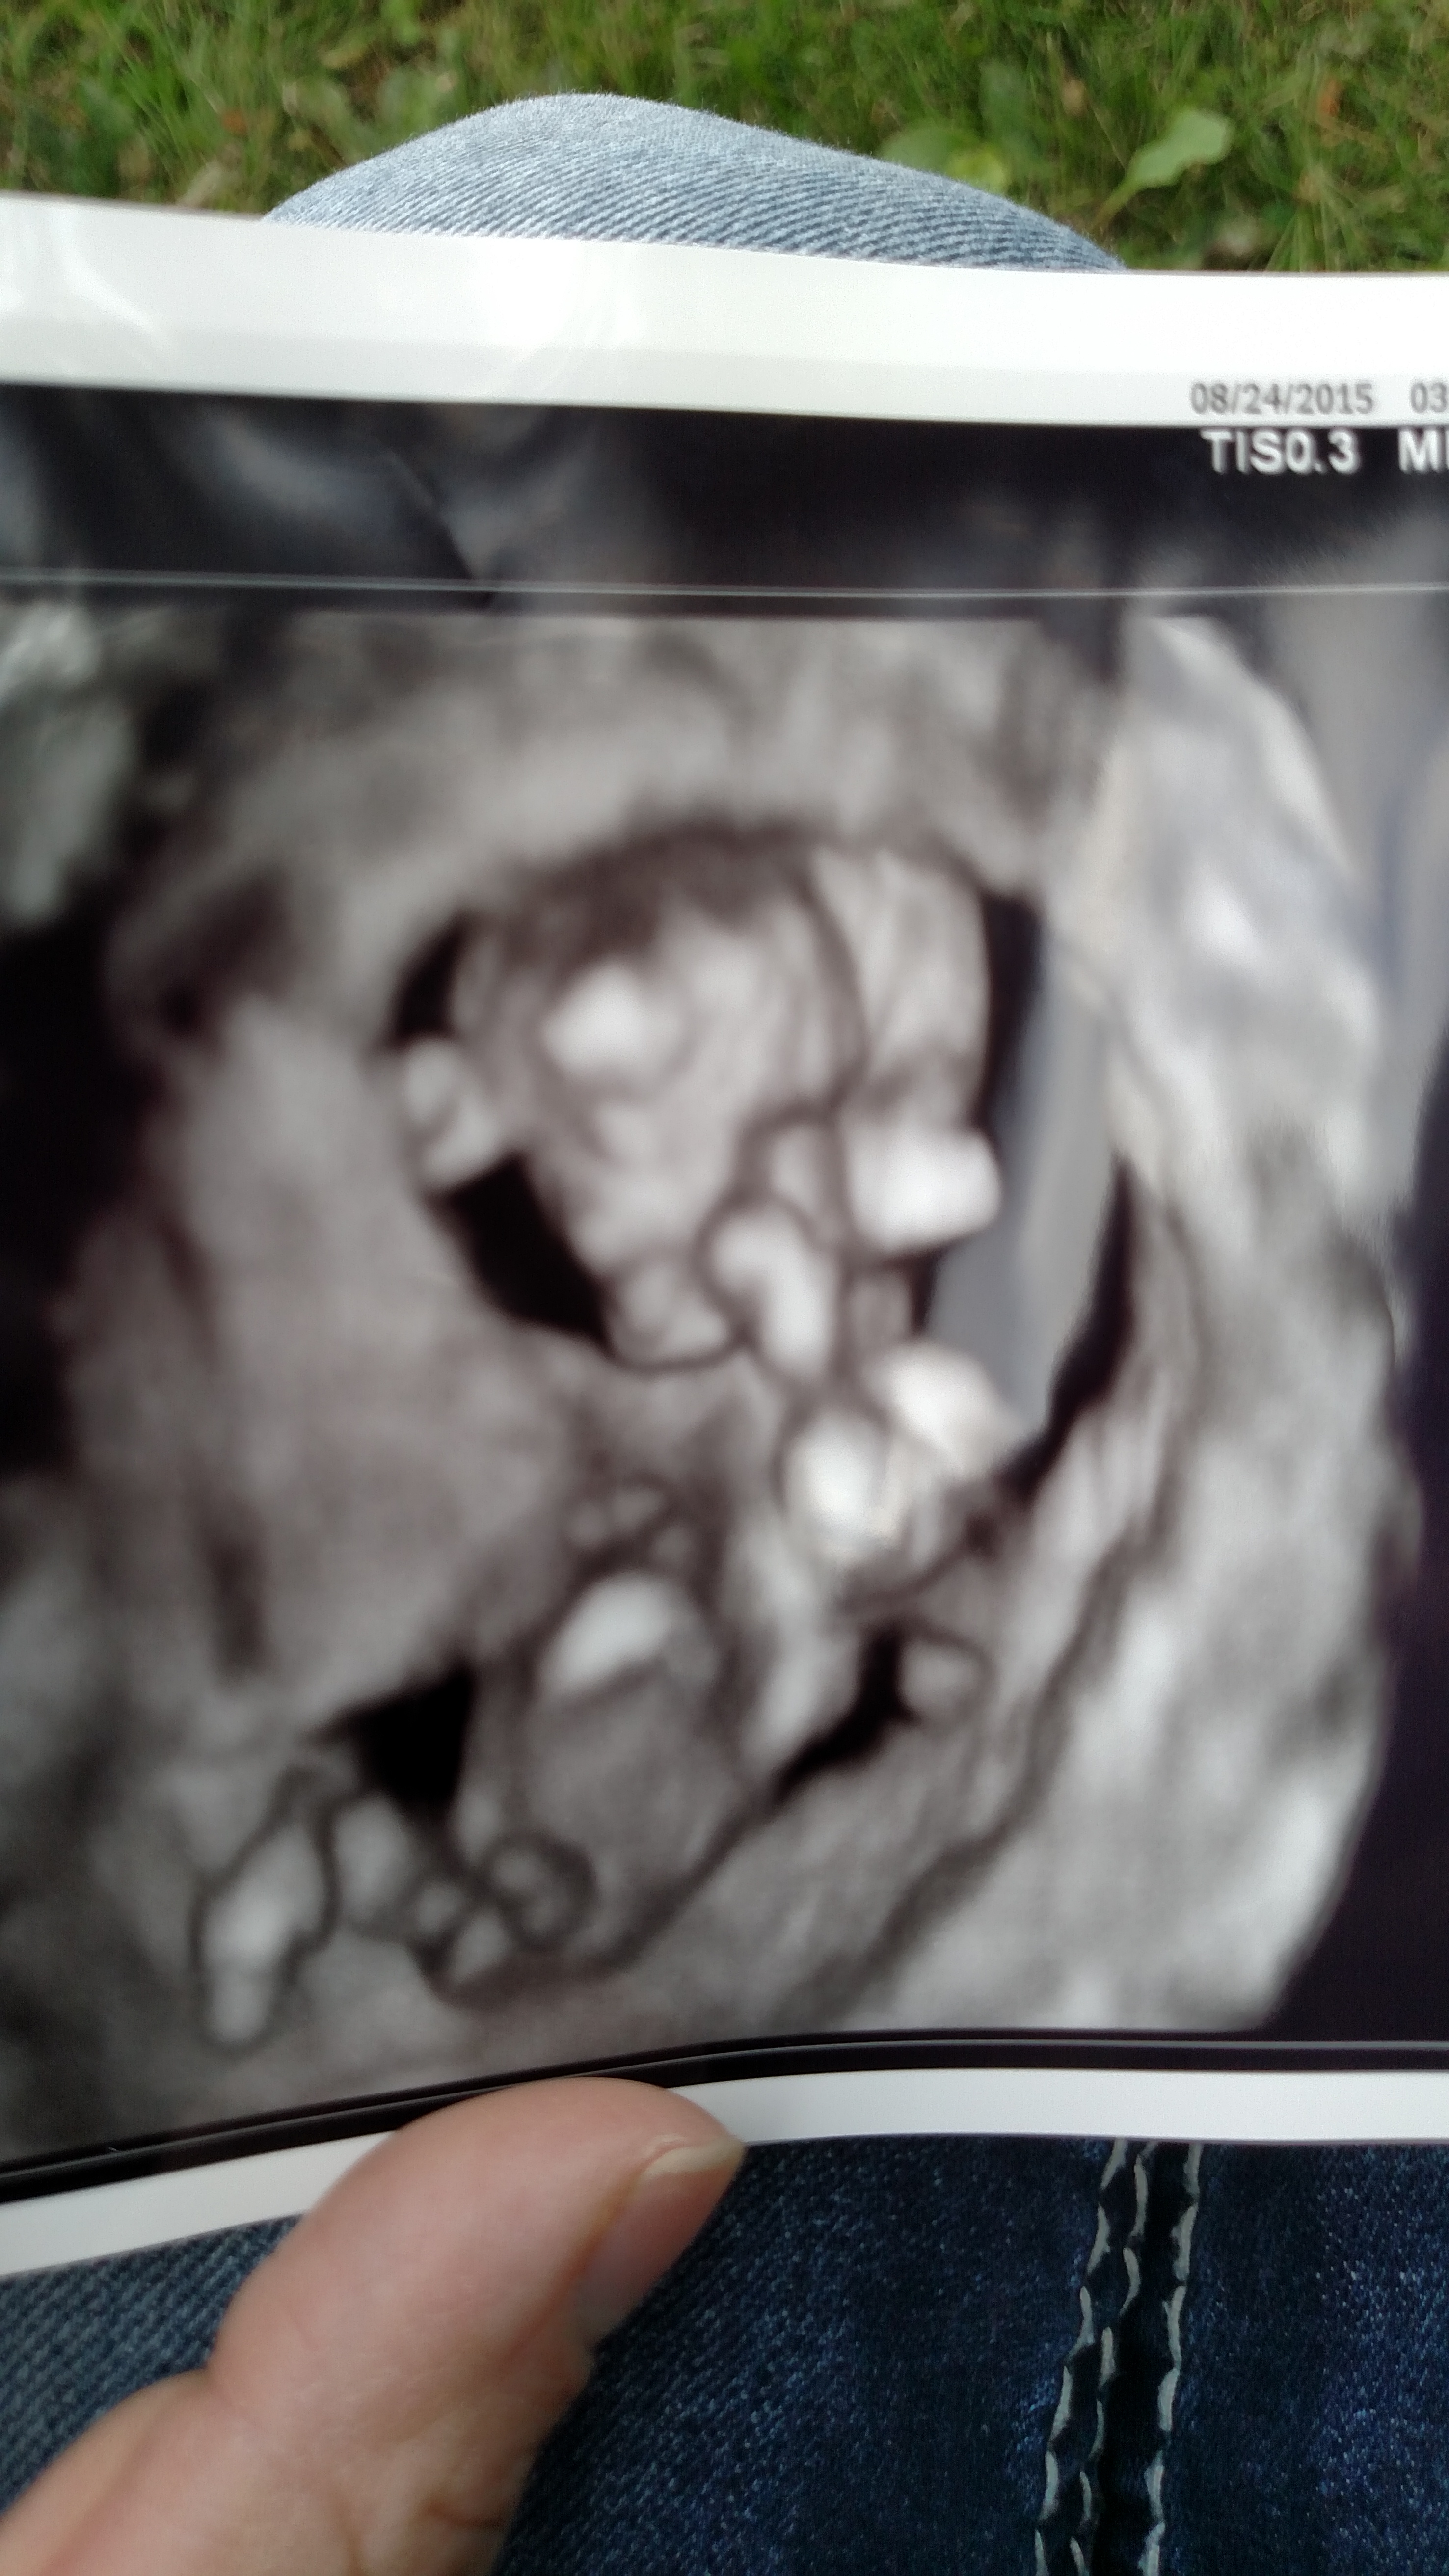

No nub on 2d but leaning boy aswell incase the maybe nub? on 4d seems quite angled up. What gestation was this? :)

It is 12 weeks 3 days